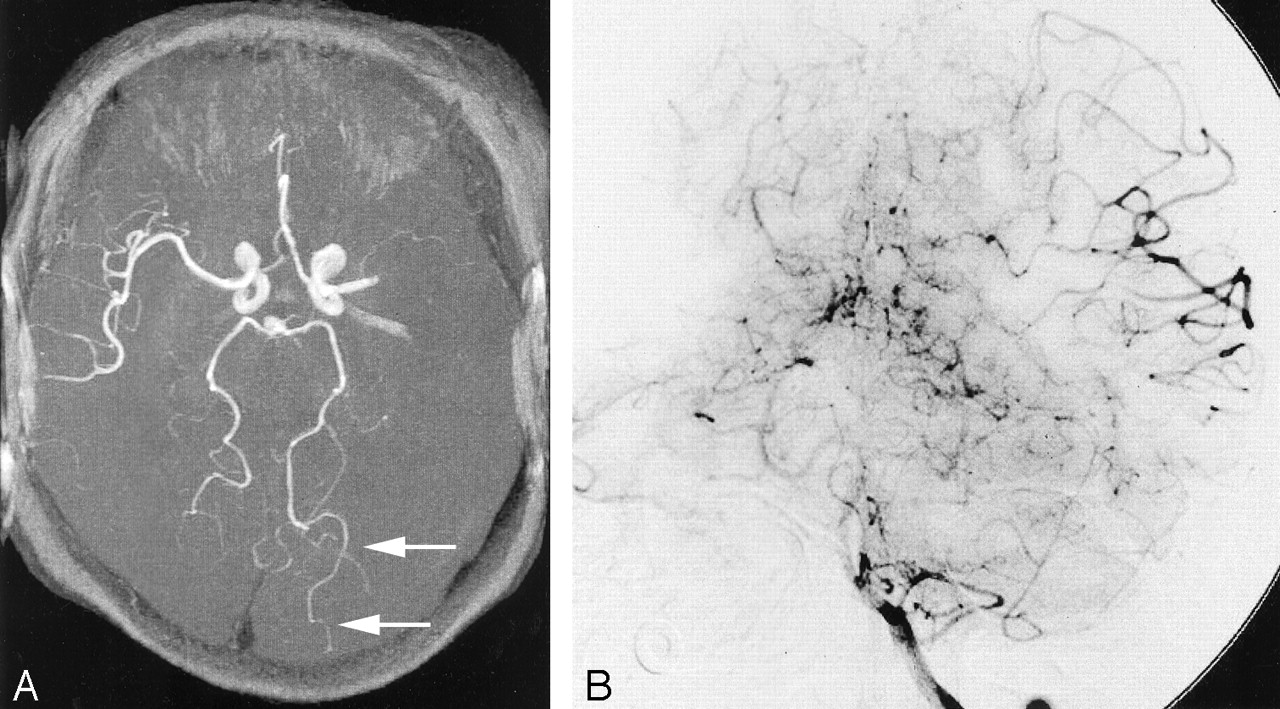

Ipsilateral P4 sign in a 73-year-old female patient who presented with acute-onset right hemiplegia.

A, 3D TOF MRA obtained 3 hours after onset showed left M1 occlusion. Ipsilateral P4 (parieto-occipital artery) is observable over almost half of the segment (white arrows).

B, Anteroposterior view of left vertebral arteriogram shows prominent collateral flow from the PCA to the ipsilateral MCA during the capillary phase (black arrows).